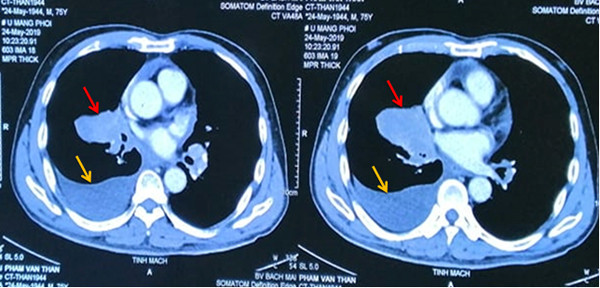

Khối u ở thùy giữa phổi kích cỡ 6x4 cm, đè đẩy gây xẹp phổi

Do 2 ung thư đều ở giai đoạn muộn, bệnh nhân có rất nhiều hạch ở trung thất, hạch thượng đòn, tổn thương xương đa ổ. Khối u ở phổi đã to 6x4 cm, 3 khối u não kích cỡ 0,5-0,7 cm, u tuyến tiền liệt to gần 3 cm.